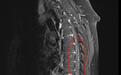

小气泡状阴影即为动静脉瘘

“曹先生患上的是硬脊膜动静脉瘘,这是一种脊髓血管畸形。”杜兴国解释,这种畸形是指供应脊髓或神经根的细小动脉,在椎间孔附近与脊髓表面的引流静脉直接交通,形成动静脉短路。短路导致动脉血直接高速通过静脉引流,引起脊髓静脉高压,继而引起脊髓缺血、变性及坏死,从而出现脊髓功能障碍,这才是曹先生双腿乏力的真正原因。目前,曹先生已转入神经外科进行治疗。

武汉市第四医院古田院区神经外科主任赵焱介绍,硬脊膜动静脉瘘是一种罕见病,可发生于脊髓的任何节段,起病缓慢,开始常表现为单一的感觉、运动或括约肌功能障碍,如下肢不对称性烧灼感或蚁走感。经常容易被漏诊或误诊为腰椎间盘突出、脊髓炎、前列腺增生等疾病。确诊可选择全脊柱磁共振,但确诊本病的“金标准”就是选择性脊髓血管造影。一旦确诊,需尽早手术治疗。